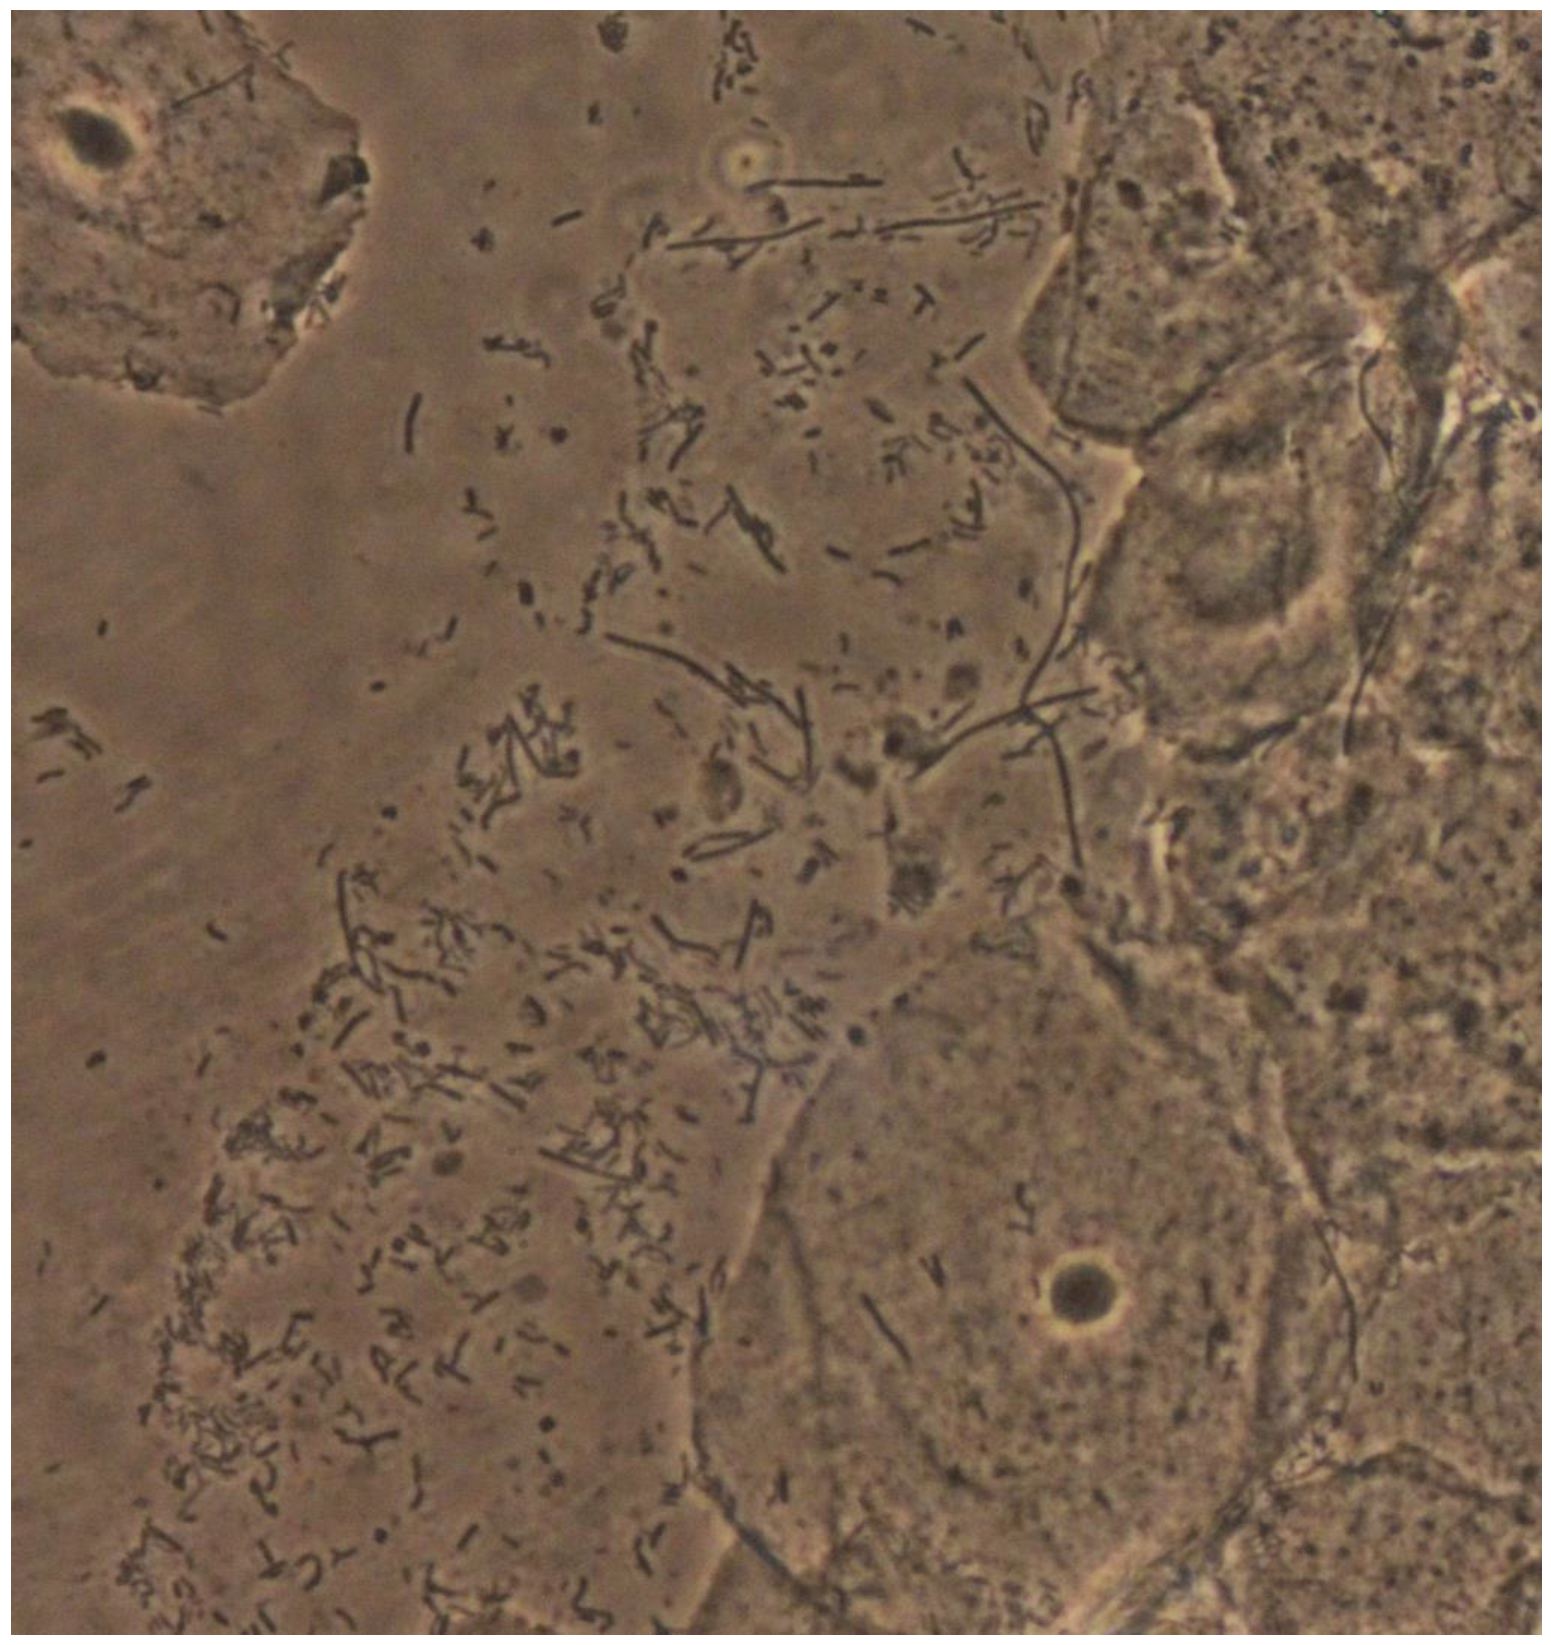

The term “lactobacillosis” was first used by Horowitz et al. in 1994 and originally described as the presence of long forms of serpiginous lactobacilli (60 μm), usually referred to as “leptothrix,” from the Greek “λεπτος” (thin) and “ϑρίξ” (hair) (Figure 1). Horowitz described these forms of long bacteria in the vagina of women with symptoms similar to those of candidiasis (burning, itching, and irritation), typically starting 7–10 days after menses [1,2]. However, most women presenting with these forms of lactobacilli were asymptomatic [1]. Some authors classify an increased number of lactobacilli, in the absence of cytolysis, independently of their characteristics, as lactobacillosis as well. If a cytolytic pattern is concomitantly present, it is classified as cytolytic vaginosis, and it may be speculated that the two presentations may represent the same entity or consist of a part of a spectrum [3].

Figure 1.

Leptothrix and normal background flora (×400).